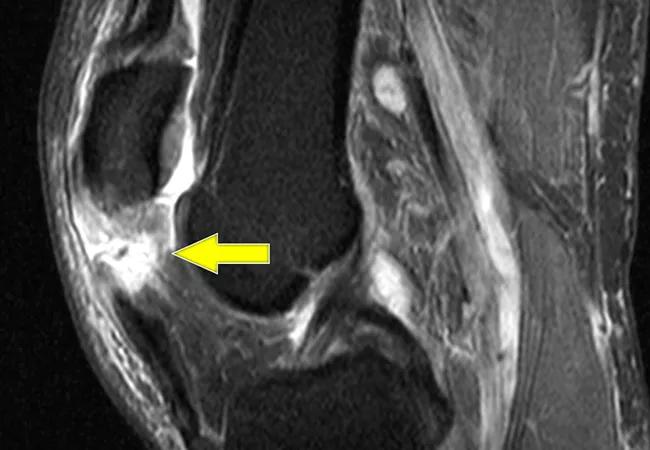

Ruptures of the patellar tendon and quadriceps tendon almost always require surgical repair. But does one tendon injury have a better chance of recovery than the other? As it turns out, neither tendon repair has particularly good outcomes, according to a Cleveland Clinic study.

Patients with patellar tendon injuries tend to be younger and healthier than patients with quad tendon injuries. (Patellar tendon ruptures are generally caused by traumatic injury rather than wear and tear.) However, the study did not find a difference in outcomes between the two groups of patients. Rather, it found that both types of injuries require significant rehabilitation time, and many patients never fully recover.

“The fact is, these are massive injuries,” he says. “In spite of repairing and healing, the tendons often don’t come back anywhere near normal, and patients still have significant disability.”

The study followed 59 patients with patellar tendon injuries and 82 patients with quadriceps tendon injuries through surgery and for one year afterward.

Patellar patients were younger, with a median age of 45 compared to 60 for quadriceps patients. Researchers looked at a variety of risk factors and used Knee Injury and Osteoarthritis Outcome Score (KOOS) for pain and physical function to measure recovery outcomes.